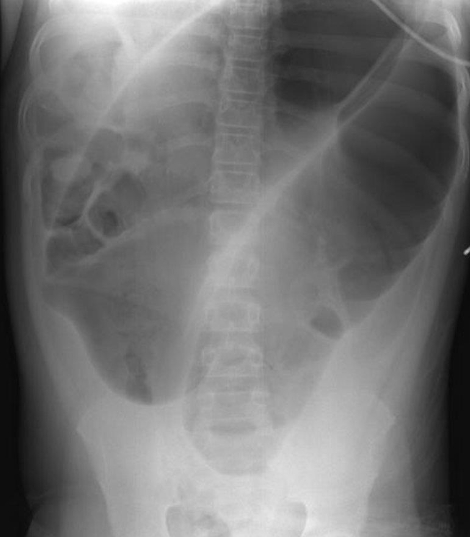

Imaging examination Plain X-ray

Findings or description The oval calcified shadow (arrowhead) is a faecolith in the appendix.

Sign Note the dilated loops of small bowel in the centre of the abdomen due to peritonitis – the so-called sentinel loops

Diagnosis Appendicolith